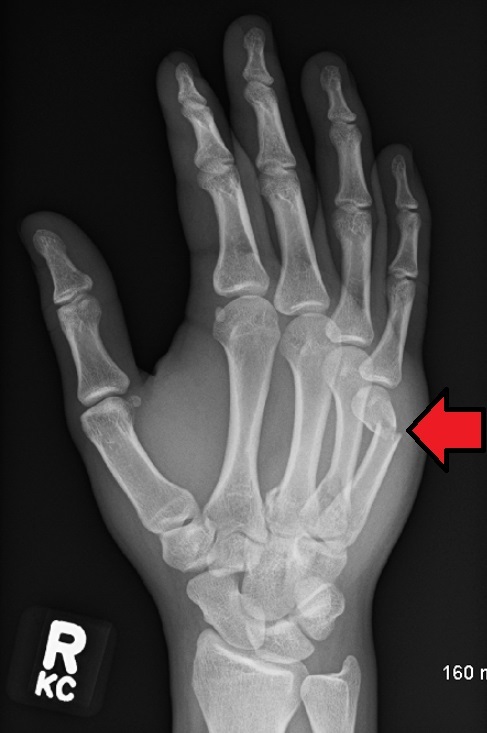

Describe this fracture?

BENNETT

- Oblique fracture through base of the first metacarpal, with dislocation of the radial portion @ articular surface

- produced by direct force applied to end of metacarpal; dorsal capsular structures disrupted by dislocation; marked tenderness along medial base of thumb

• thumb spica x 4 weeks